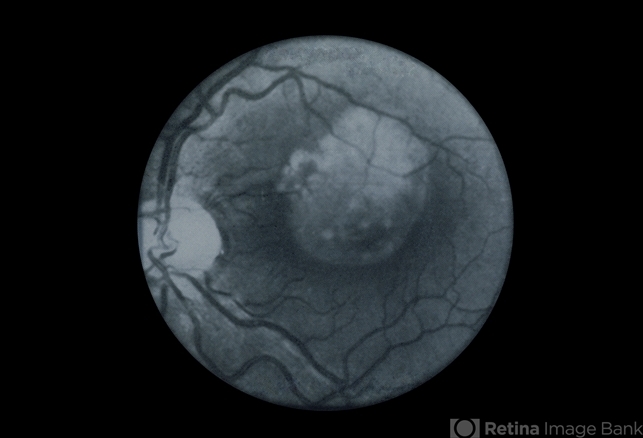

- cryptococcal chorioretinitis

- Active chorioretinitis.